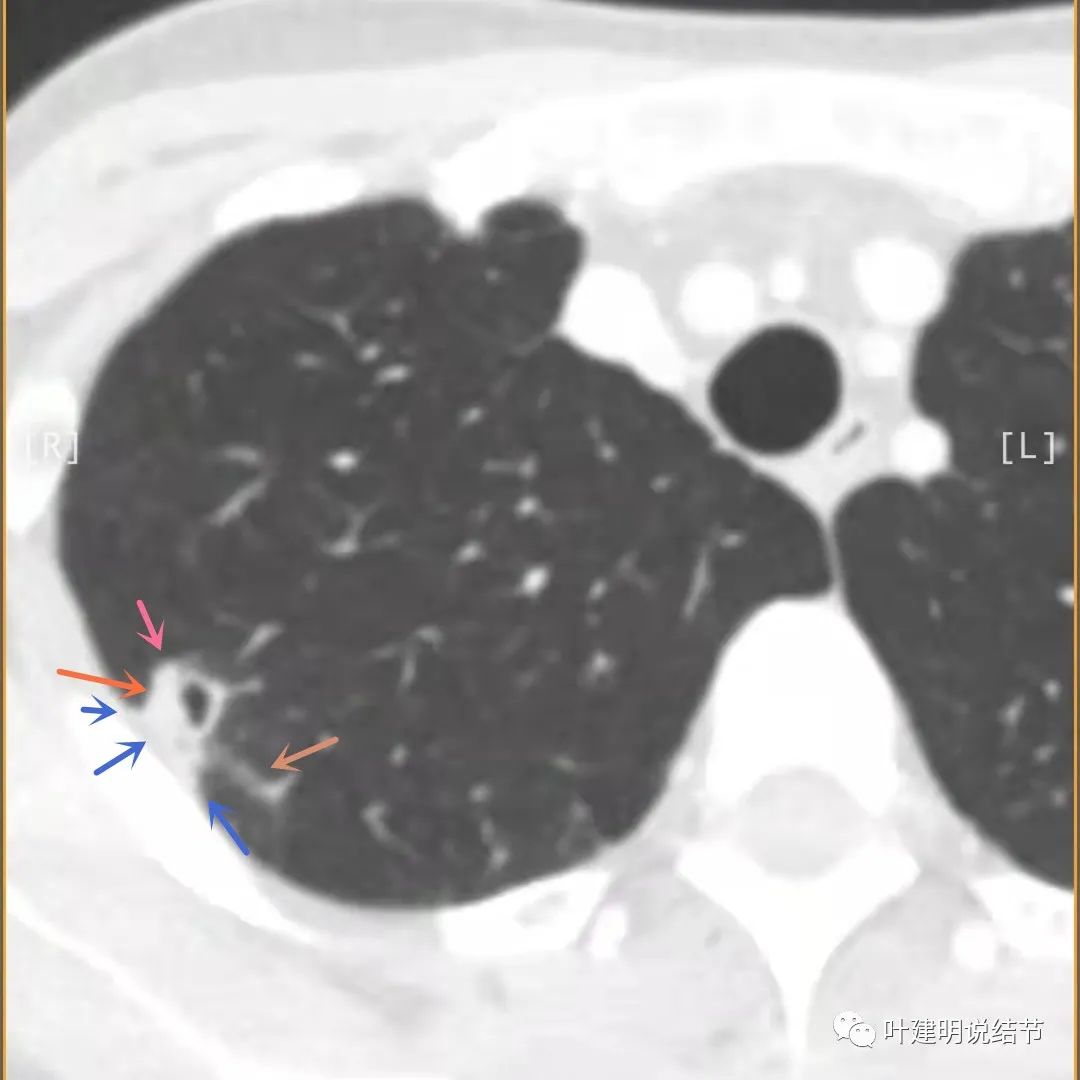

上面是她提供的病史资料,其中最重要的是PPD强阳性!其他主要看影像,我们先来看她2020年7月份的平扫片子(由于片子较多,详细展示是为了同道分析,我在影像特征描述上将只选取部分加以说明):

右肺尖偏实性结节(粉色箭头),邻近胸胸膜明显增厚不平,且广基附在胸壁上(蓝色箭头)

有卫星病灶(绿色箭头)